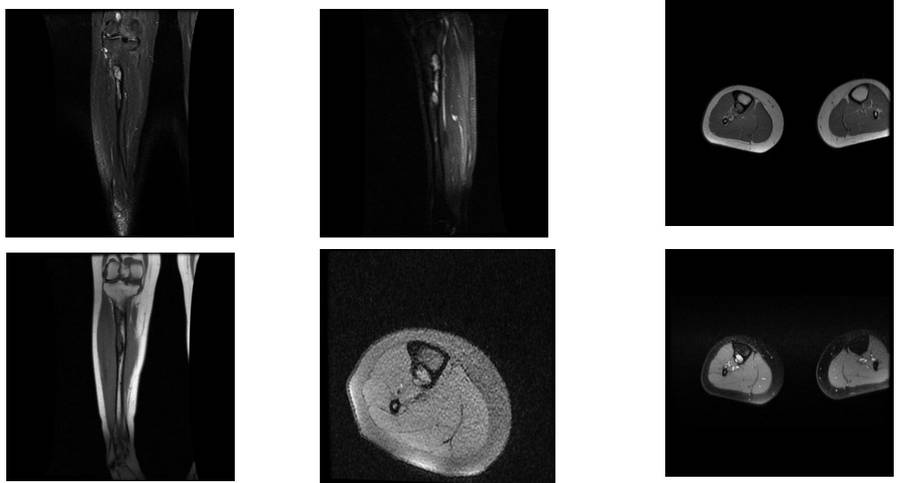

Ameliyat Öncesi: MR’da heterojen kitle olduğu görülmekte